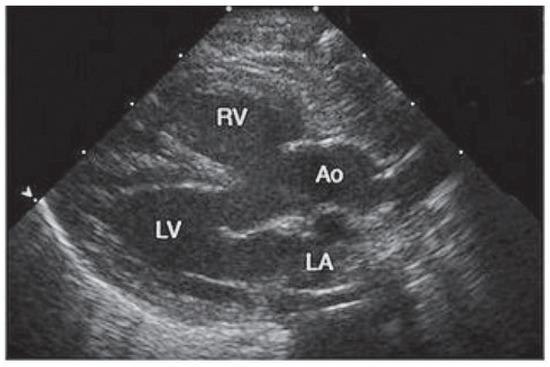

Summary. We report two cases of a 83- and a 78-year-old female with tetralogy of Fallot (TOF) who underwent operation at an advanced age in their 30’s, making them the oldest patients repaired for tetralogy of Fallot [...]